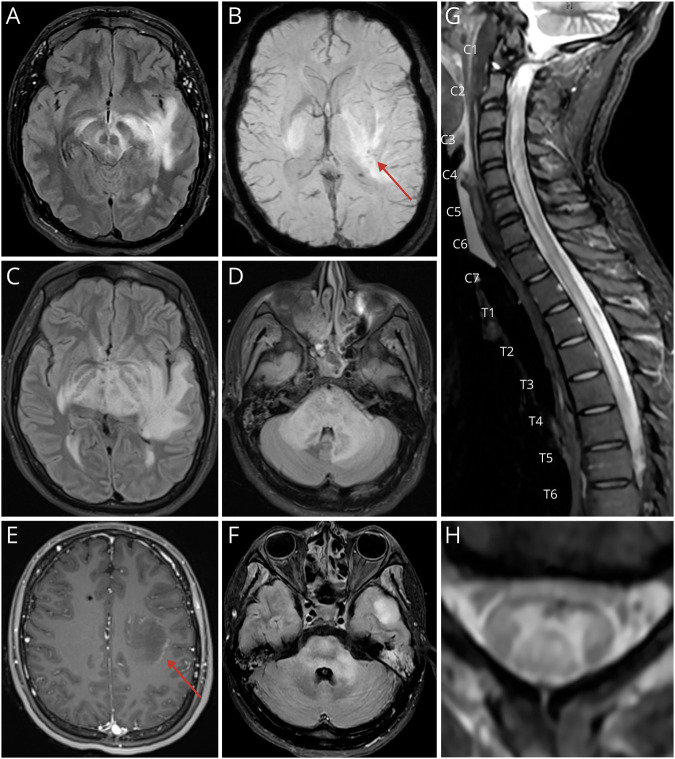

Methods: This case report describes a young adult with partial CFI deficiency, presenting with acute hemorrhagic leukoencephalitis and longitudinally extensive transverse myelitis.

Results: In this case of unexplained CNS autoinflammation, in-hospital whole-genome sequencing and complement testing revealed partial CFI deficiency. CSF profiling during flares showed increased neutrophils and proinflammatory cytokines. CSF gene expression profiling more closely aligned with cases of bacterial meningitis than autoimmune encephalitis, consistent with innate immune system hyperactivity. Emergent IL-1 receptor antagonism led to sustained suppression of further immunologic attacks.